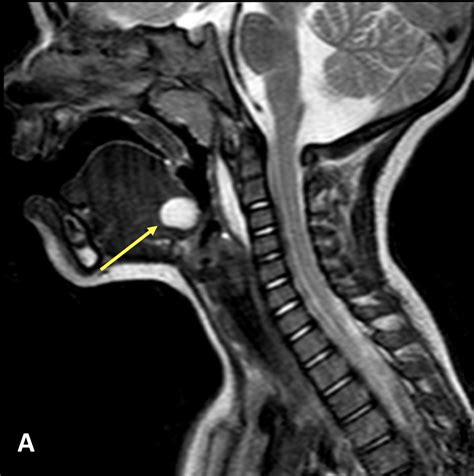

When a physician suspects a Duct Cyst Thyroglossal, they will perform a physical examination to check the cyst’s mobility and location. To confirm the diagnosis and rule out other conditions like lymphadenopathy or branchial cleft cysts, diagnostic imaging is generally required.

Ultrasound The primary imaging modality; effective at identifying the fluid-filled nature and location relative to the hyoid bone.

CT Scan Provides detailed anatomical mapping; often used to determine the extent of the cyst if infection is present.

The hallmark of a Duct Cyst Thyroglossal is a painless, smooth, and cystic mass situated along the midline of the neck. Because of its anatomical connection to the hyoid bone, the mass often moves upward when the patient swallows or protrudes their tongue. This movement is a critical diagnostic sign for clinicians.